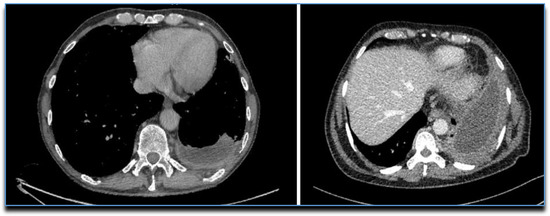

14. CT